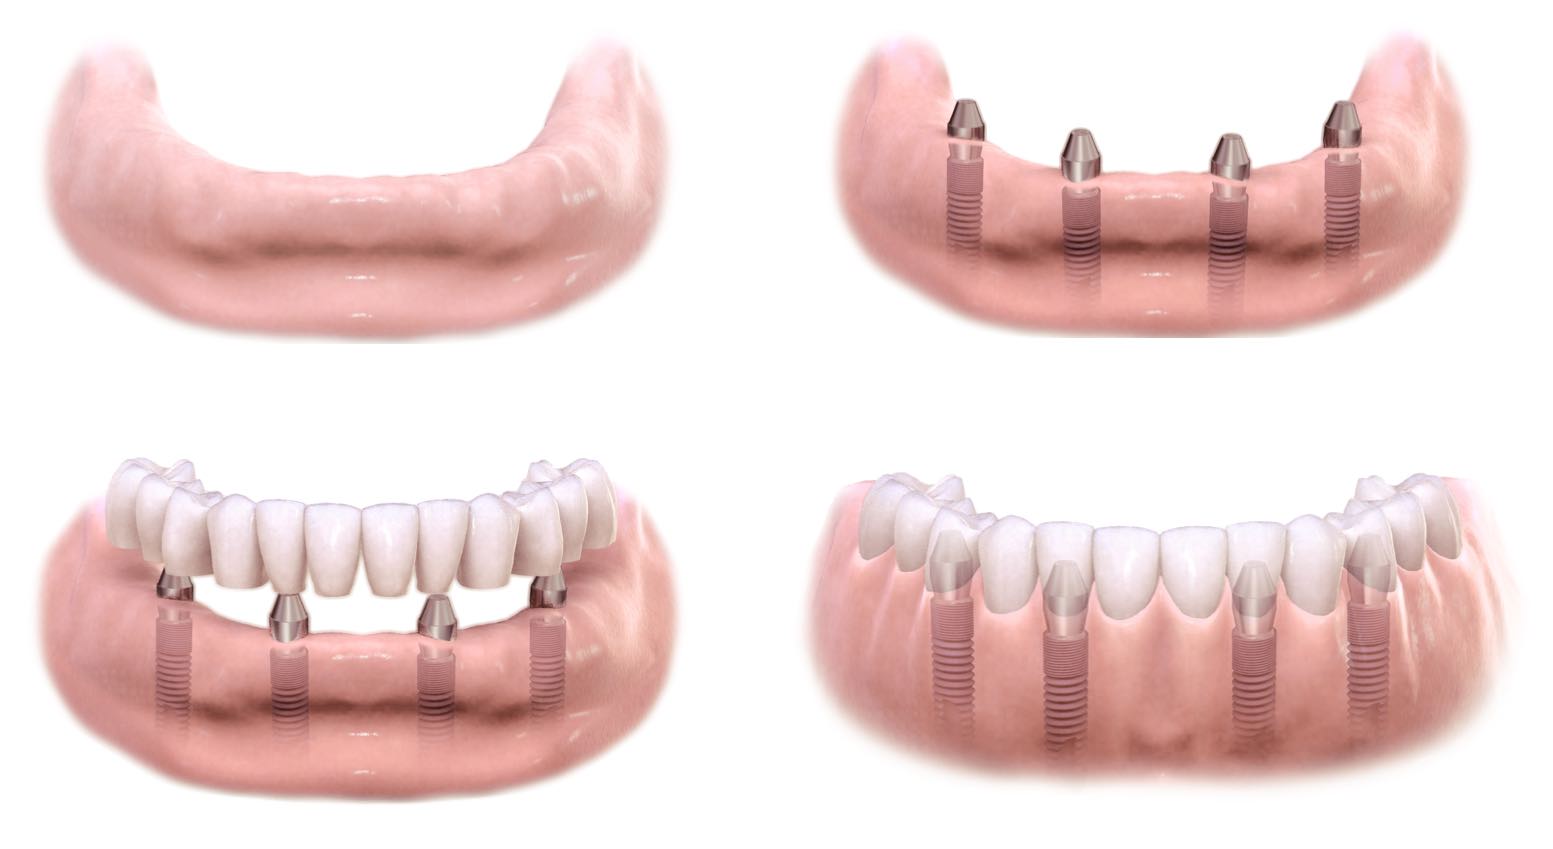

Пошаговое руководство по установке съёмного протеза на импланты